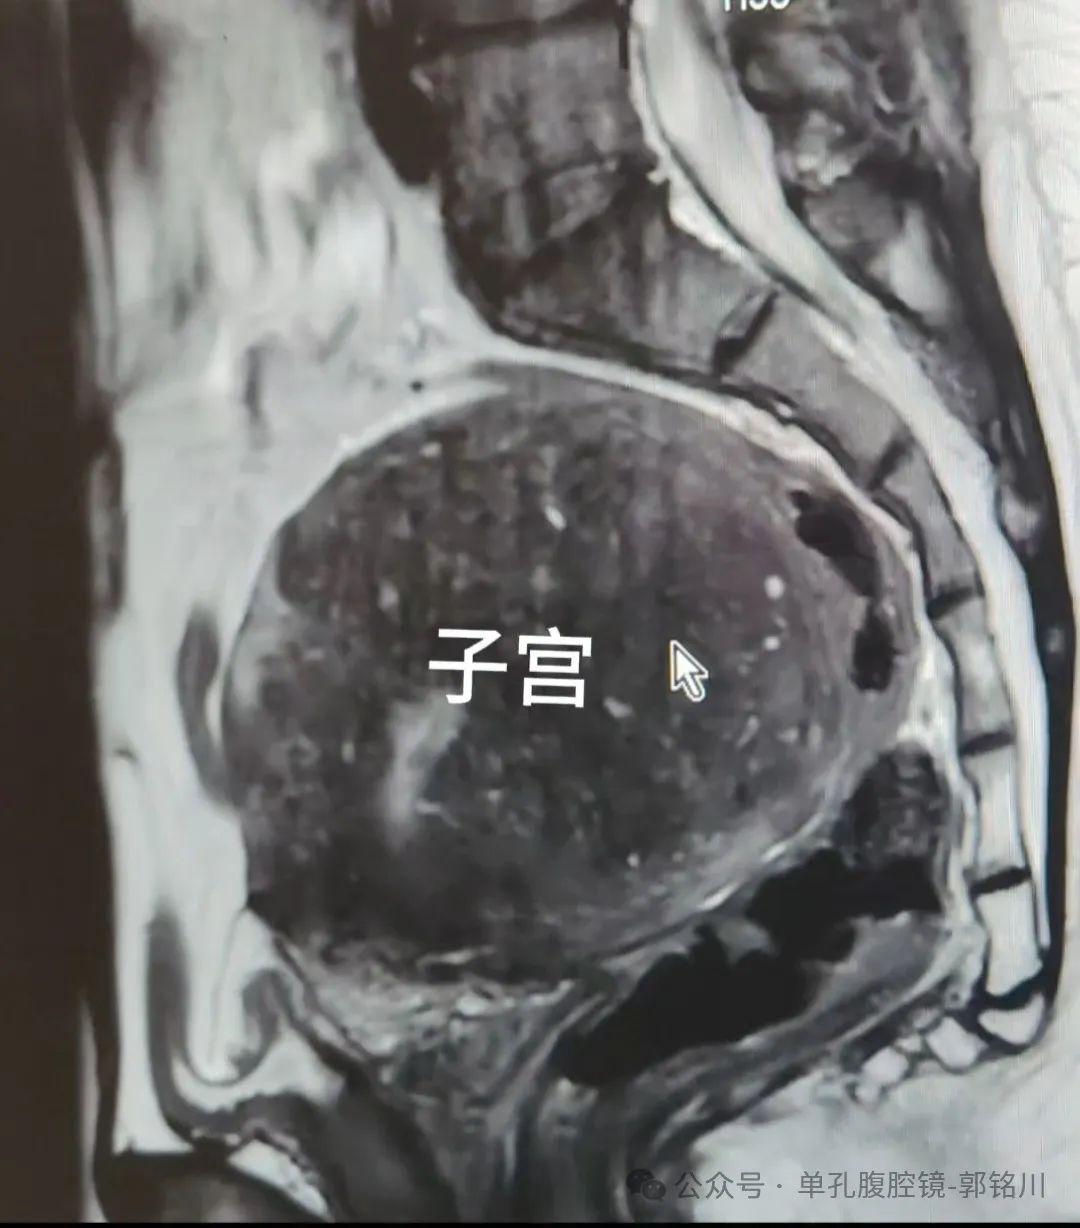

底下是术前影像相片

子宫腺肌症是一类以痛经、月过程多,和子宫迟缓增大为证据的子宫内膜异位症。患者会跟着子宫的不休变大症状越来越重!

该患者是饱受子宫腺肌症困扰的女性,出血、贫血、痛经,履历了漫长的保守调整,最终下定决心来切除子宫。

手术切除的标本重达430g,平常子宫惟有50~70g!